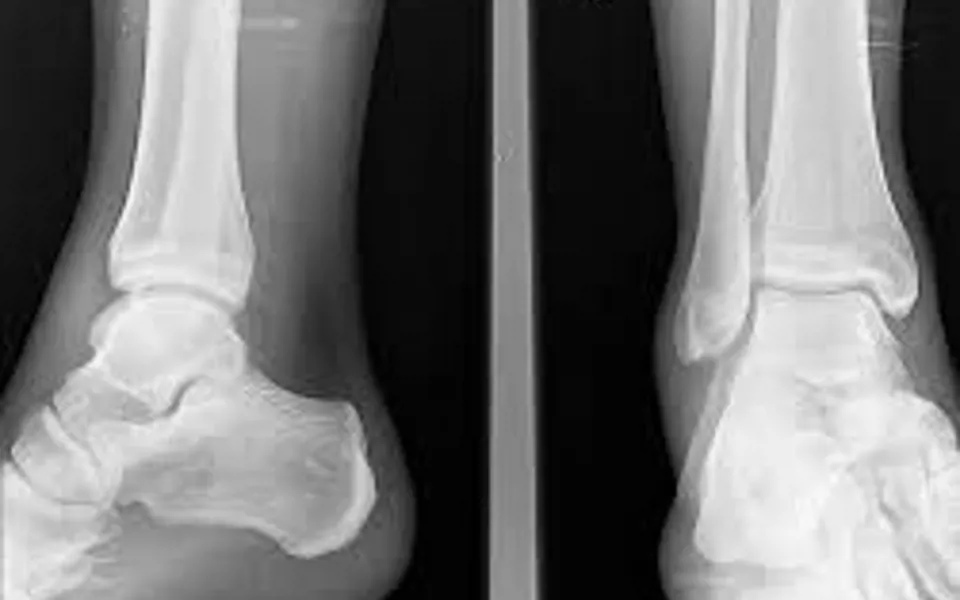

Para su correcto diagnóstico es importante conocer las lesiones asociadas que pueden presentarse con el fin de evitar un mal manejo inicial o futuras complicaciones. Las más importantes son las fracturas del maléolo peroneal o de la base del quinto metatarsiano. Es importante destacar que, debido a la alta incidencia del esguince de tobillo y la baja prevalencia de las fracturas asociadas surgió la necesidad de crear unos criterios que evitaran radiar de forma innecesaria a los pacientes. Estos criterios son las llamadas Reglas de Ottawa, que permiten al profesional decidir si es necesario realizar una radiografía si sospecha de una fractura (Jonckheer et al., 2016).